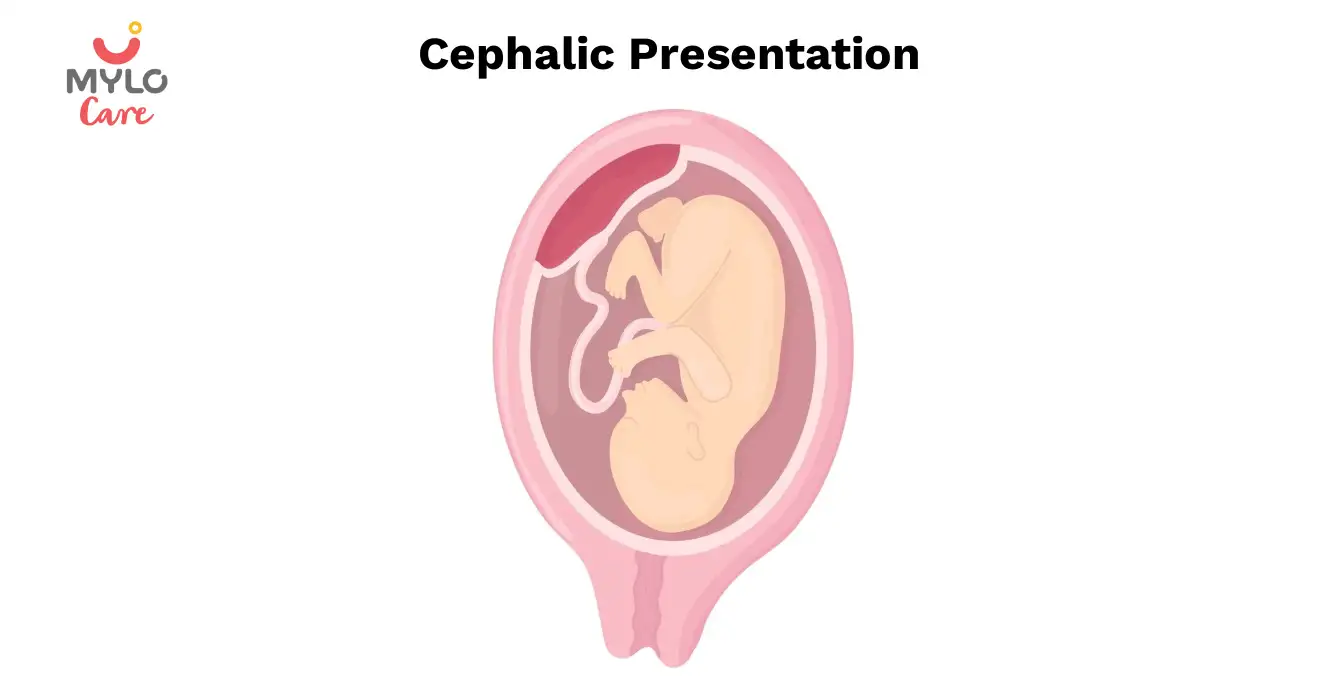

The most common and ideal position for labor is when your baby is positioned head-down with their chin tucked to the chest and face facing the mother’s back. This baby’s position in womb is known as the anterior position. In this position, the baby’s head is pointing towards the birth canal, ready to enter the pelvis. Most babies enter this position between weeks 32 and 36 of pregnancy.

Why is the anterior position the best for giving birth?

The anterior position is considered an ideal position because it helps in progressing your labor. In this position, the head of the baby points towards the birth canal. The chin of the baby is tucked into their chest and their face is facing your back. You might feel the kicks of the baby under your ribs and your belly button may stick out.

You may also like: The ABCs of Cephalic Presentation: A Comprehensive Guide for Moms-to-Be

The ABCs of Cephalic Presentation: A Comprehensive Guide for Moms-to-Be